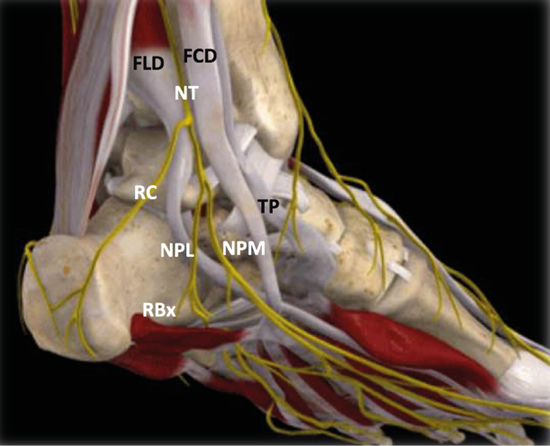

El nervio tibial, en su tránsito por la cara medial del tobillo y del pie, dará las ramas calcáneas mediales, el nervio plantar medial, el nervio plantar lateral y la primera rama del nervio plantar lateral o rama de Baxter3. El nervio peroneo profundo se localiza en profundidad a la musculatura extensora del primer radio a la altura del tobillo. El nervio peroneo superficial discurre por el borde anterior del peroné para llegar escindido al tobillo en los nervios cutáneo dorsal medial y cutáneo dorsal intermedio. El nervio sural, situado en el aspecto posteromedial de la pierna adyacente a la vena safena menor, dará las ramas calcáneas laterales antes de girar retromaleolar al peroné hacia el pie para denominarse como el nervio cutáneo dorsal lateral (Figuras 2 y 3)2,3.

Figura 3. Túnel tibiotalocalcáneo. El nervio tibial (NT) se divide en la rama calcánea (RC), el nervio plantar medial (NPM) y el nervio plantar lateral (NPL) del que se escinde la rama de Baxter (RBx). Las estructuras musculotendinosas tibial posterior (TP), flexor largo del primer dedo (FLD) y flexor largo de los dedos (FCD) acompañan al nervio tibial en su recorrido por la cara medial del tobillo y el pie. Imagen modificada de la App Ankle & Foot Pro III.

Figura 5. Túnel tibiotalocalcáneo. La porción proximal o túnel tibiotalar superior en azul. Estructuras nerviosas: nervio tibial (NT), rama calcánea (RC), nervio plantar lateral (NPL), nervio plantar medial (NPM), rama de Baxter (RBx). Estructuras musculotendinosas: tibial posterior (TP), flexor largo del primer dedo (FLD) y flexor largo de los dedos (FCD). Imagen modificada de la App Ankle & Foot Pro III.